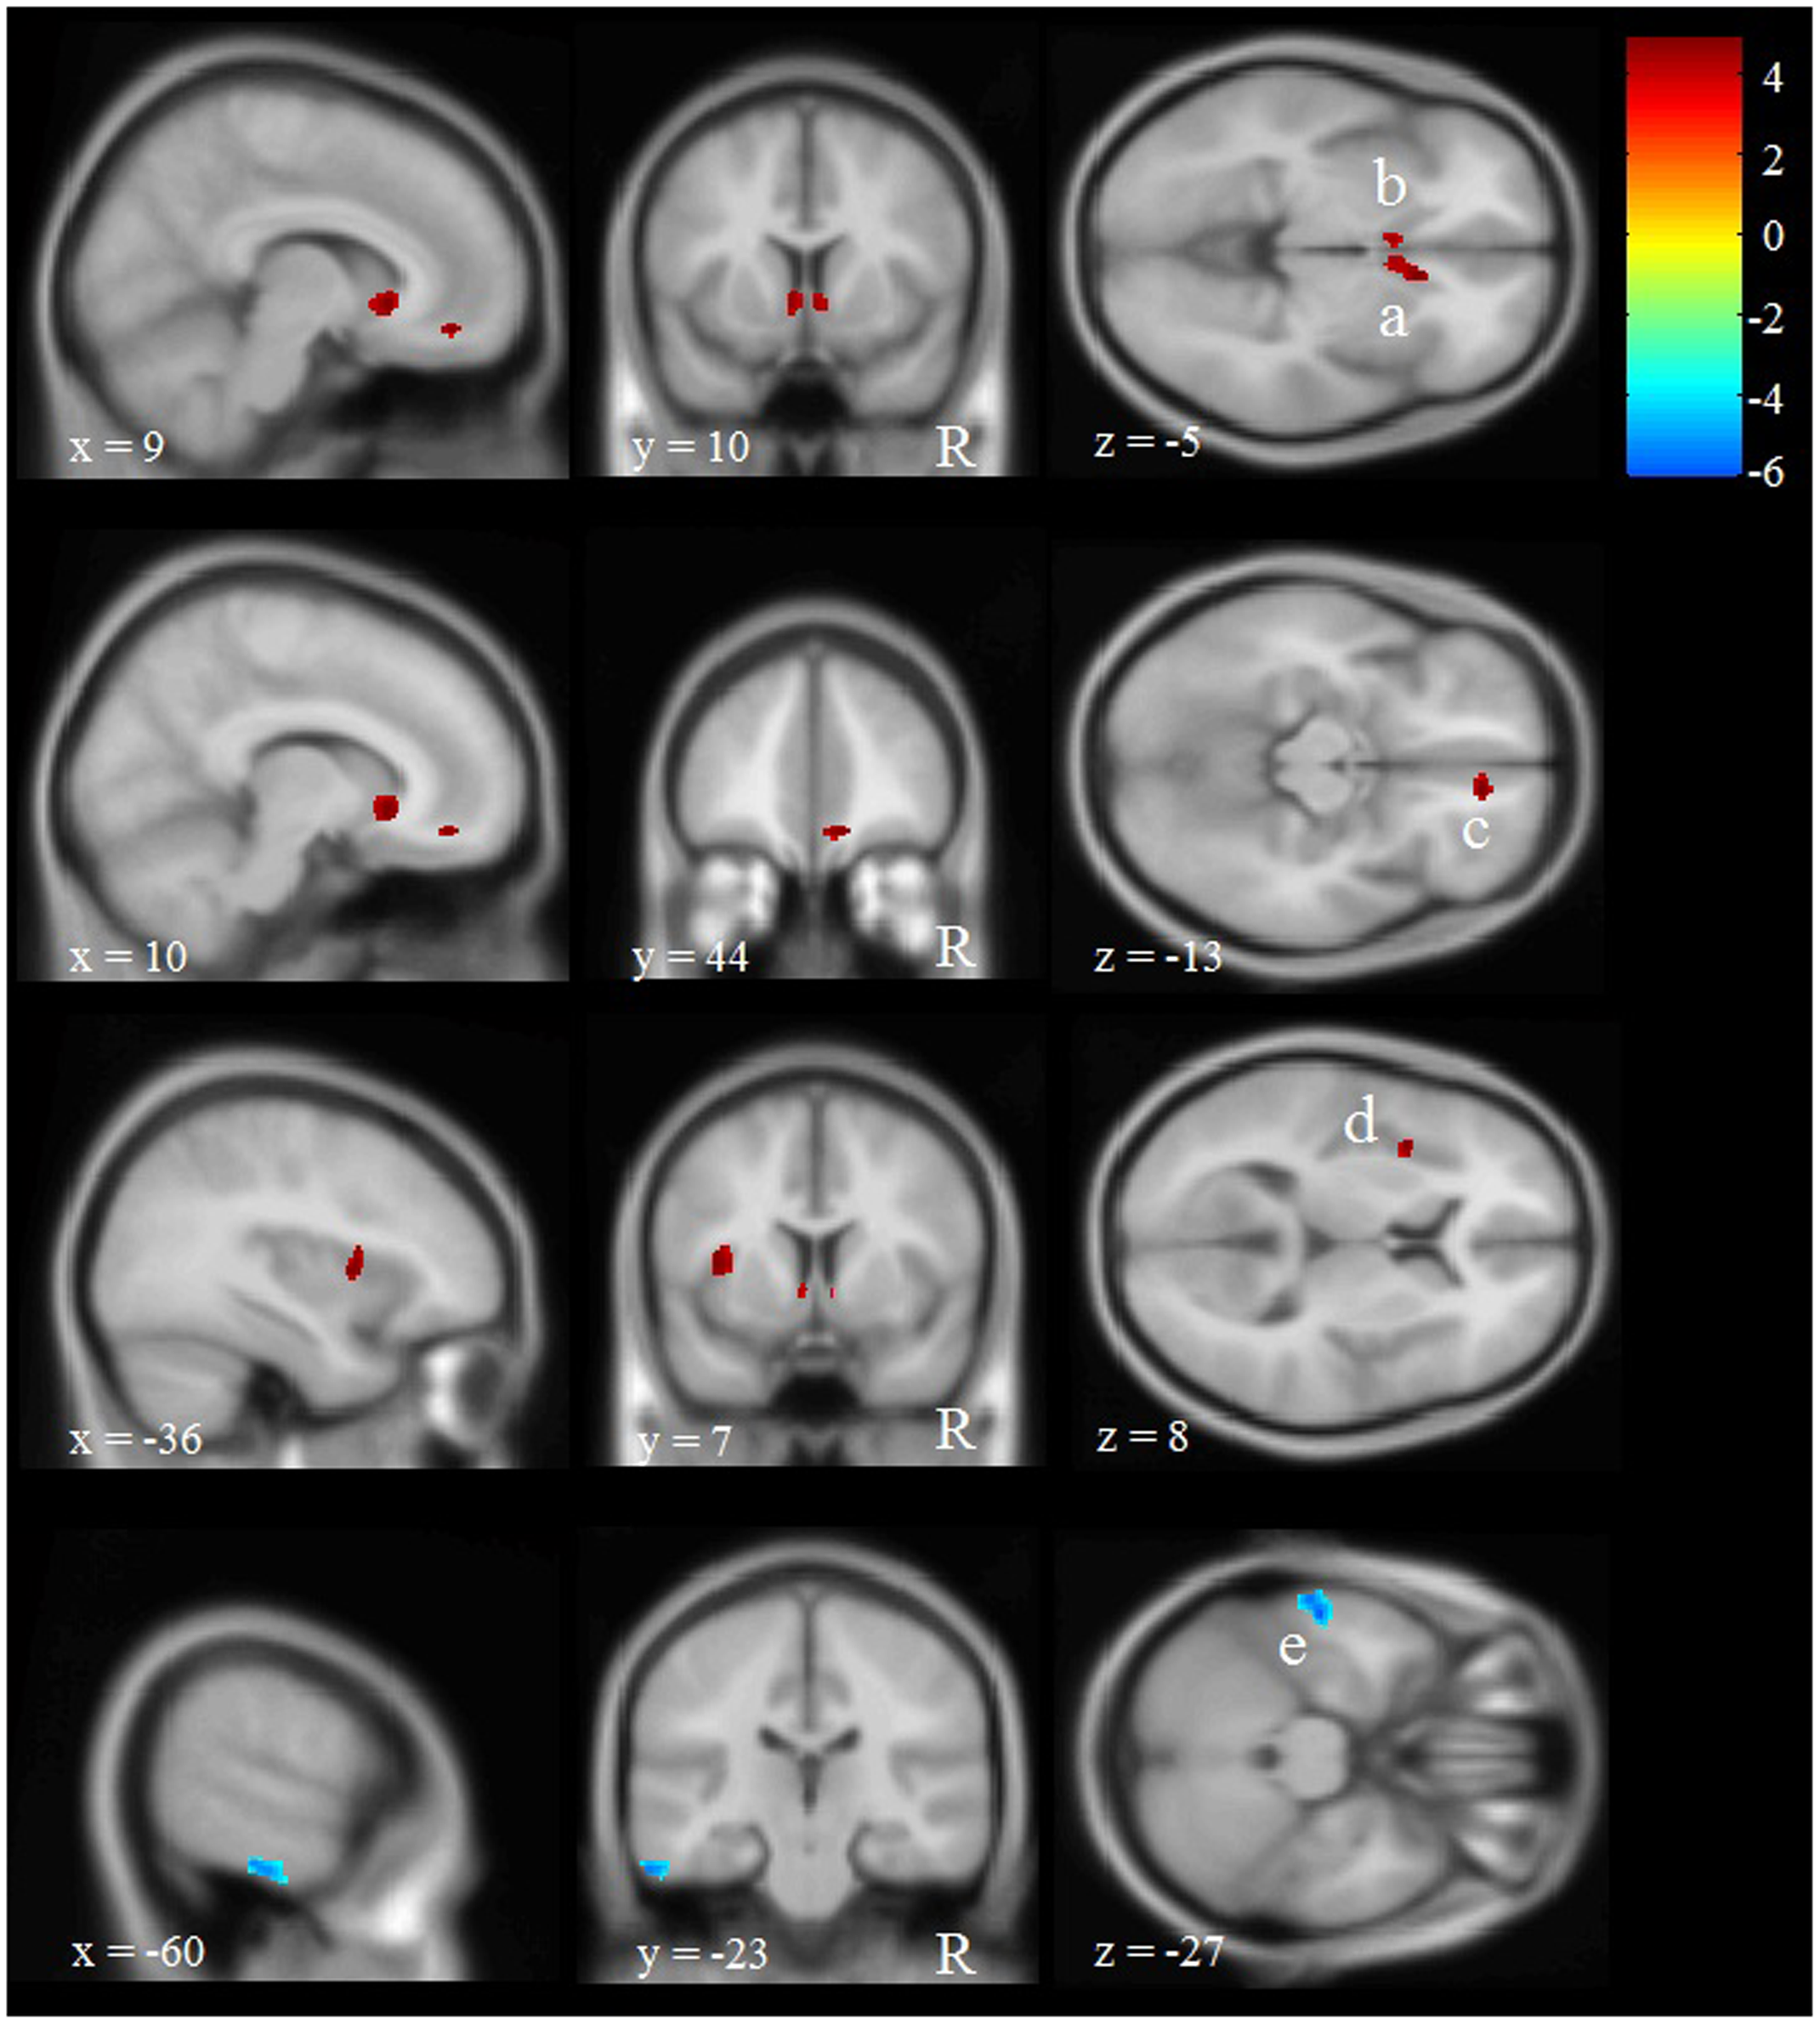

The VBM analysis revealed five regions with significant differences in GM volume between participants with multiple versus 0 or 1 WTC (see Figure 3 and Table 5). We found four voxel clusters in which participants with multiple WTC indicated more GM volume than participants with 0 or 1 WTC: two clusters located in the left and right caudate, one of them extending into the right rostral anterior cingulate cortex (ACC). In addition, there were another two clusters in the right medial frontal gyrus and in the left insula. Vice versa, participants with 0 or 1 WTC depicted more GM volume in the left inferior temporal gyrus.

FIGURE 3. Effects of WTC on regional gray matter (GM) volume in long-term production workers (n = 20). Shown are clusters with significantly more (red, a–d) or less (blue, e) GM volume in participants with multiple WTC as opposed to participants with 0 or 1 WTC. Multiple WTC were associated with more GM volume in the left (a) and right caudate (b), as well as in the medial frontal gyrus (c) and the insular cortex (d). 0 or 1 WTC were associated with more GM volume in the inferior temporal gyrus (e). The letter ‘R’ indicates the right hemisphere. Letters a, b, c, d, e refer to the voxel clusters depicted in Table 1. x, y, and z specify the MNI coordinates.

In a follow-up analysis and in order to validate the factual importance of the regions detected in our VBM analysis, we correlated the individual average GM volume in each of these regions with performance in the identical pictures and N-back tests. Results suggest moderately high correlations between performance in the identical pictures test (but not the N-back task) and the four clusters that were positively associated with WTC: particularly the two clusters comprising the left and right caudate and rostral ACC but also the two clusters in the left insula and the right medial frontal gyrus depicted moderately high correlations between r = 0.22 and r = 0.46 with performance in the identical pictures test. That is, the more GM volume individuals depict particularly in the left and right caudate the more correct trials they reached in the identical pictures test. In contrast, the one cluster in the left inferior temporal gyrus that was negatively related to WTC did not show a significant correlation with processing speed or working memory (see Table 6).